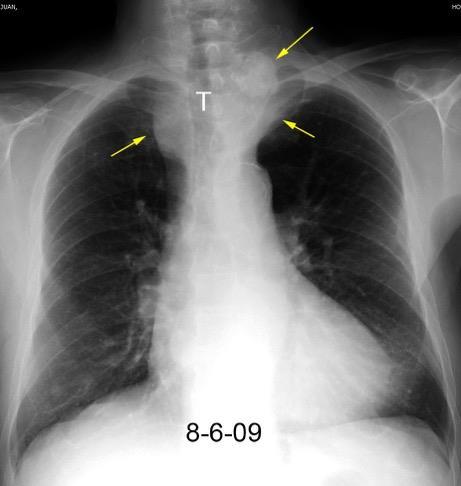

Carcinoma subglótico

Tumor poco frecuente. 1,8% de los tumores laríngeos.

Tendencia a invadir el anillo cricoideo y el esófago.

Ganglios + frecuentes

Mac Neill SD et al. Survival of patients with subglottic squamous cell carcinoma. Curr Oncol. 2018